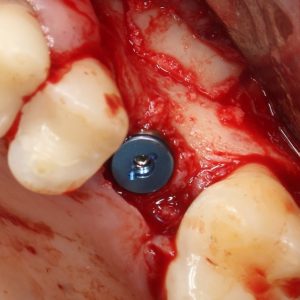

Рекомендации по установке имплантов. Для всех. Часть III